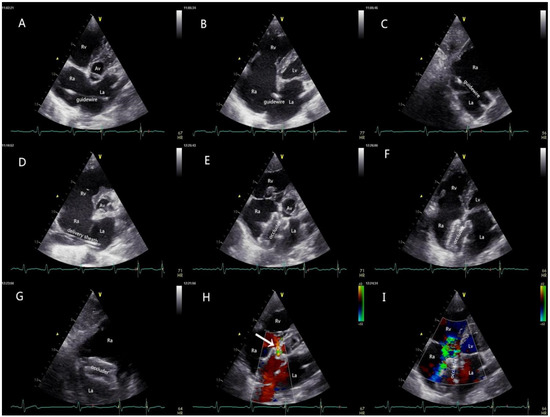

Patients with an adequate thoracic ultrasonic window received local anesthesia and underwent TTE-guided PAC, and the remainder received the procedure under traditional TEE guidance and general anesthesia. Right heart and peripheral artery catheterization were routinely performed to achieve perioperative hemodynamic monitoring. The patient was then placed in a 30-degree right-chest elevated position. The size of the Amplatzer Septal Occluder (LZASD, SHANGDONG VISEE MEDICAL DEVICES Co., Ltd., China) was completely based on the result of echocardiography (oversized by 4 mm to 6 mm more than the maximum dimension of the defect) rather than balloon sizing in all patients. The procedure is demonstrated in Figure 3. The patients receiving regional anesthesia were sent directly to the general ward, and those who underwent general anesthesia were sent to the ICU. Anticoagulation via the oral administration of dipyridamole or aspirin was carried out for 3 months after the procedure.

Figure 3.

Procedural protocol. (A) The guidewire was inserted from the RA into the LA via the femoral vein under the guidance of TTE; (B,C) the tail end of the high-echo guidewire was confirmed to be inside the LA in the four-chamber view and the short-axis subcostal view; (D) a delivery sheath was inserted along the guide-wire into the LA, and then the inner core and the guidewire were withdrawn; (E) the occluder was delivered carefully through the sheath under the real-time guidance of TTE, and the LA disc was opened; (F,G) the occluder was completely released, and the two discs of the occluder were accurately parallel to the plane of the atrium septal; (H) the blood flow from CS was fluent (white arrow); (I) the shunt between RA and LA disappeared, and no mitral regurgitation was detected with TTE. Mild tricuspid regurgitation still existed, as confirmed before the interventional catheterization. TTE: transthoracic echocardiography; RA: right atrium; LA: left atrium; RV: right ventricle; LV: left ventricle; TV: tricuspid valve; AV: aortic valve; CS: coronary sinus.